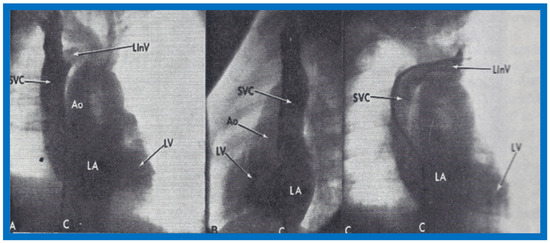

At the age of 8 months, cardiac catheterization with selective cineangiography was performed. The left atrium (LA) was catheterized via a tight patent foramen ovale, and the catheter was advanced from the LA into the superior vena cava (SVC) and into both right and left innominate veins. The right heart saturations were low (60–62%) without any evidence for a step up. The pulmonary venous saturations were normal (98%) with a step down in the left atrium and left ventricle (79%). The pressures in all cardiac chambers were normal (See Table 1 of [2]). Selective cineangiography into the right (Figure 6A,B) and left (Figure 6C) innominate veins confirmed the diagnosis of anomalous connection of the right SVC to the LA. No persistent left SVC was identified. Because of a lack of other symptoms and only mild polycythemia (hemoglobin of 15 gm%), surgical correction was deferred at that time with a plan for surgery at a later date.

Figure 6.

Angiographic frames from injections into the right innominate (A,B) and left innominate (LInV) (C) veins demonstrating direct opacification of the right superior vena cava (SVC), left atrium (LA), left ventricle (LV) and aorta (Ao) without opacification of the right heart structures. C, Catheter. Reproduced from Truman T.A., Rao P.S., Kulungara R.J. [2].